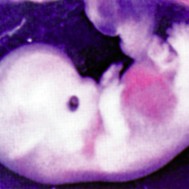

Baby: Week 6

You’re now making spontaneous movements, and can twitch your trunk and limb buds

Each day, changes make you more recognisable as a small person just like you. Now your lungs are forming![1] Brain function, as measured by EEG waves, can be recorded within days.[2] Nerve cells in the brain are connecting, forming primitive neural pathways. Your hands can bend at the wrist, and webbing is disappearing from your feet. Your tail is just about gone. Tastebuds are forming on your tongue.[3] You’re now making spontaneous movements, and can twitch your trunk and limb buds.[4]